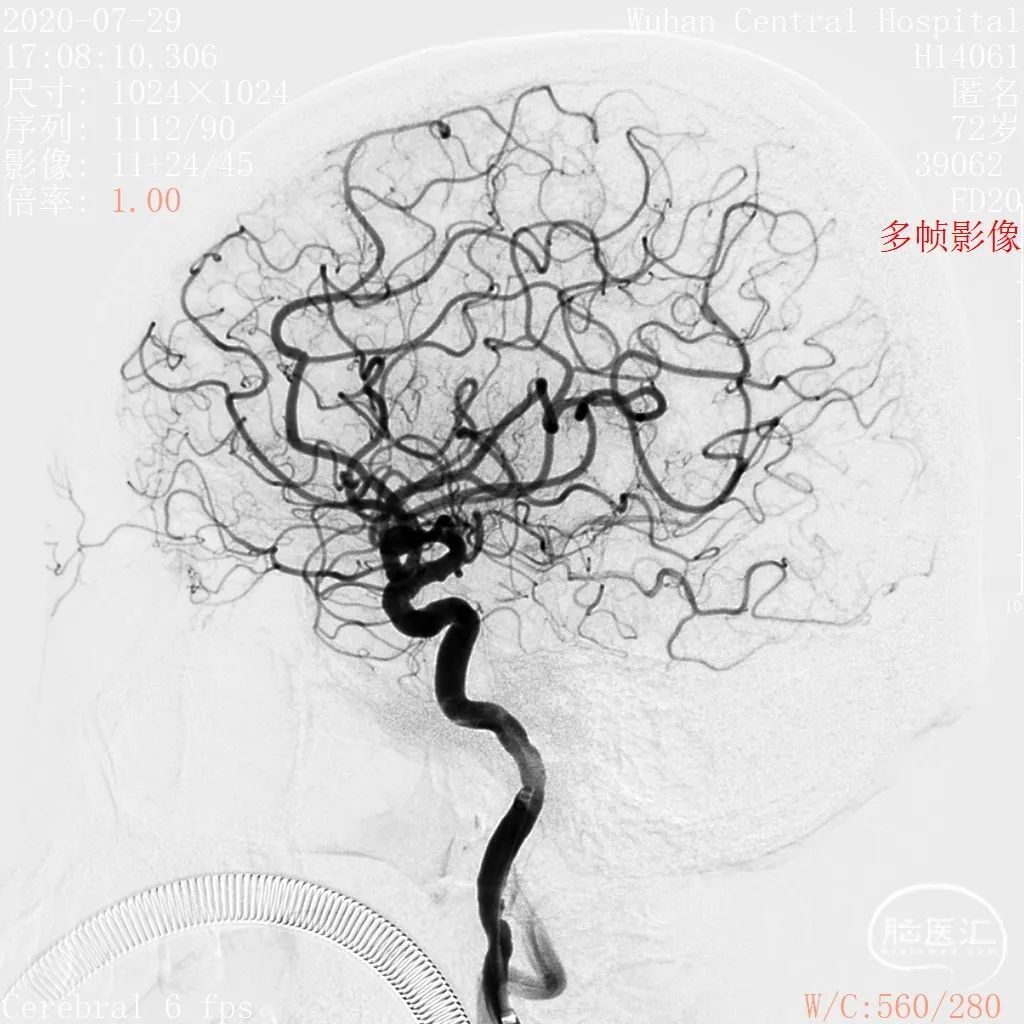

术前影像

DSA 2020-07-29